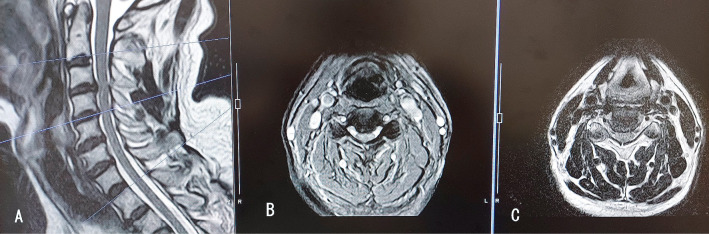

Gelatin-based hemostatic agents are widely used in neurosurgery. This is a case of postoperative aphagia strongly suspected to be caused by an allergic reaction to a gelatin-based hemostatic agent after anterior cervical decompression and fusion for central cervical cord injury. A 55-year-old man underwent cervical anterior decompression and fusion at the C3/4 and 4/5 levels for central cervical cord injury. Immediately after the surgery, he could not swallow saliva at all, but his voice was not hoarse. Postoperative cervical computed tomography and magnetic resonance imaging showed significant edema from the post-hypopharynx wall to the front of the vertebral body. The retropharyngeal space was remarkably enlarged to 15.8 mm with cervical spine X-rays. Without neurological symptom improvement, his condition was diagnosed as marked edema of the area where Surgiflo (porcine-derived gelatin-based hemostatic agent; Johnson & Johnson Wound Management, Somerville, NJ, USA) had been applied during the operation. It was strongly suspected to be caused by an allergic response to the porcine-derived gelatin. When methylprednisolone 1000 mg was administered for 3 days from the 5th postoperative day, swallowing became almost normal within a few hours after the initial administration, and his neurological symptoms improved. The patient left the hospital on the 12th day after the operation. Before using porcine-derived gelatin products during surgery, special consideration should be given to patients with an allergy history before surgery.

明胶类止血剂广泛应用于神经外科。这是一例术后失语症,强烈怀疑是由于前路颈椎减压融合治疗中心性颈髓损伤后对明胶止血剂的过敏反应引起的。55岁男性因中心性颈髓损伤行颈椎前路减压和C3/4和4/5节段融合术。手术后,他完全无法吞咽唾液,但声音并不沙哑。术后颈椎计算机断层扫描和磁共振成像显示从下咽后壁到椎体前部明显水肿。颈椎x线片显示咽后间隙明显增大至15.8 mm。神经系统症状没有改善,他的病情被诊断为Surgiflo(猪源明胶止血剂;强生伤口管理公司(美国新泽西州萨默维尔)在手术中应用。人们强烈怀疑这是由对猪源明胶的过敏反应引起的。术后第5天起给予甲强的松龙1000 mg,连续3天,术后数小时吞咽基本恢复正常,神经系统症状改善。患者于术后第12天出院。在手术中使用猪源明胶产品之前,应特别考虑术前有过敏史的患者。